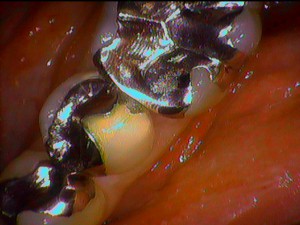

約10日くらい前に歯の表面に歯石やプラーク、そして歯肉の中までに深めの歯石が付着しておりました。

歯周組織の改善には歯周ポケットと呼ばれる歯肉の中に深さを測る小さい器具を患者さんに痛みがないようにいれていきます。前回の数値よりも良くなっている結果が分かりました。

見た目の歯ぐきの状態も綺麗に改善回復していました。患者さん本人も歯ブラシのやり方一つで歯ぐきから血が出なくなったと喜んでいました。月1回の歯周病予防のためのメンテナンスを受けたいとのことでした。